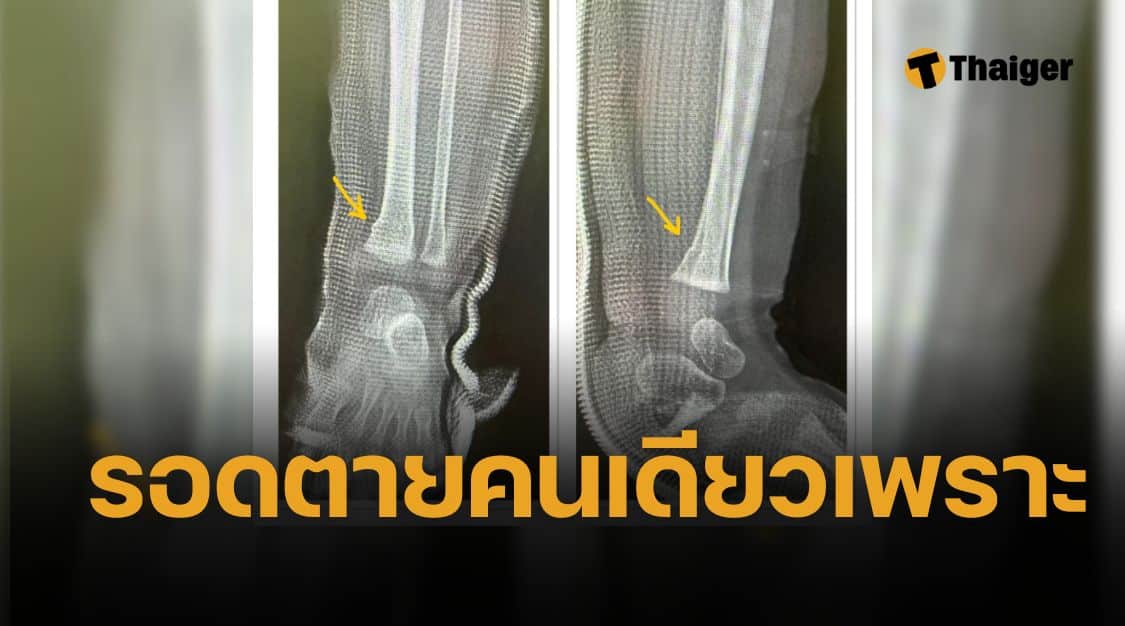

คุณหมอยิ่งยศเล่าว่า เช้านี้ได้รับแจ้งว่ามีเคสเด็กอายุ 9 เดือนที่แอดมิทอยู่ใน ICU จากอุบัติเหตุรถยนต์เมื่อวานนี้ พอเปิดดูฟิล์มเอ็กซ์เรย์ก็เห็นเพียงกระดูกขาหักเล็กน้อย ไม่มีบาดแผลรุนแรง และอาการโดยรวมไม่น่าห่วง จึงเข้าใจว่าเหตุที่ต้องนอน ICU คงมาจากเหตุผลทางด้านระบบอื่นๆ